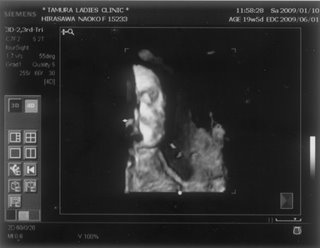

お腹の赤ちゃんは、今日で24週と4日。あっという間に7ヶ月突入です

![]() お腹もドンドン、食欲もドンドン出ていてあしたの4回目の検診コワーイ ![]() 妊娠発覚から三ヶ月半、なのにもう妊娠7ヶ月!頭がついていきません ![]() でも、毎日激しくなる胎動に感激している日々です ![]() 一回目の検診から4週後、2度目の検診に行ってきました。 2008年12月13日 赤ちゃんは15週と5日 ![]() 順調でした ![]() 左側から頭、胴体、足が写っていまーす ![]() 今回は4Dの機械も入り毎回撮影してくれるそうでーす ![]() 赤ちゃんは、ゴツゴツした背中だけを 見せ、顔はみせてくれませんでした~ ![]() それから4週後、3回目の検診。 2009年1月10日 赤ちゃんは19週と5日 ![]() 336gくらいになったようです ![]() 4D ようやく顔をみせてくれました ![]() かなりエイリアン ですが、フニュフニュ可愛かったです![]() 性別が わかりそうだったんですが、ソラ同様肝心なトコロをみせてくれませんでした ![]() もちろんどっちでもいいんですが、しりたーい ![]() 明日わかるかな ![]() ソラも赤ちゃんがテレビに映ったり、雑誌に載っていたり、 出かけ先で見かけたりすると、「ベイビー ![]() 」と大きな声で、何度も何度も興奮気味に言います ![]() 自分もまだまだ赤ちゃんなのに、「ベイビー」は自分より 小さくて可愛いものだと感じ始めているようです ![]() わたしは、一週間に1度だけ1歳になったばかりの 女の子を預かっています。 ソラは、その子が自分のオモチャを使うことに対して 少しイヤな気がしているようです ![]() 少し前までは「ドーゾー」と相手に有無を言わせず 何でも渡していたけど、どんどん自我が出てきているみたいですね~ そんな感じでオモチャを取り合いしながら、シェアすることも学んでいます。 でも女の子が寝ると、さすがに可愛いと思ったらしく、 頭をナデナデ、チュしていました ![]() 妊娠検査薬で妊娠反応がプラス |